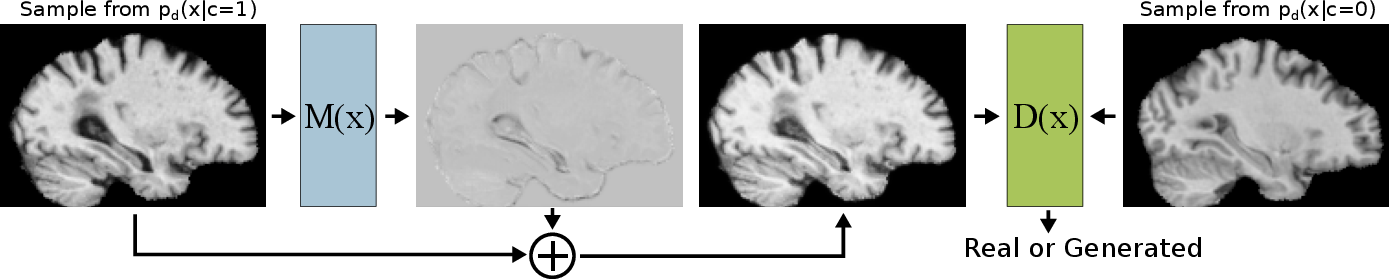

Abstract: Attributing the pixels of an input image to a certain category is an important and well-studied problem in computer vision, with applications ranging from weakly supervised localisation to understanding hidden effects in the data. In recent years, approaches based on interpreting a previously trained neural network classifier have become the de facto state-of-the-art and are commonly used on medical as well as natural image datasets. In this paper, we discuss a limitation of these approaches which may lead to only a subset of the category specific features being detected. To address this problem we develop a novel feature attribution technique based on Wasserstein Generative Adversarial Networks (WGAN), which does not suffer from this limitation. We show that our proposed method performs substantially better than the state-of-the-art for visual attribution on a synthetic dataset and on real 3D neuroimaging data from patients with mild cognitive impairment (MCI) and Alzheimer’s disease (AD). For AD patients the method produces compellingly realistic disease effect maps which are very close to the observed effects.